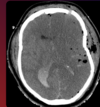

5

Achado?

HSA